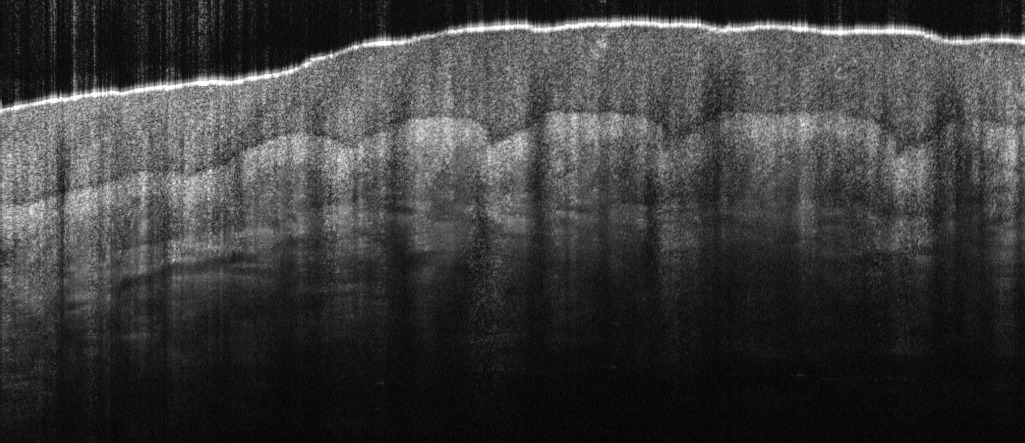

Imaging of the full anterior chamber is possible with the 12 mm imaging depth of our newest Cobra-S model.